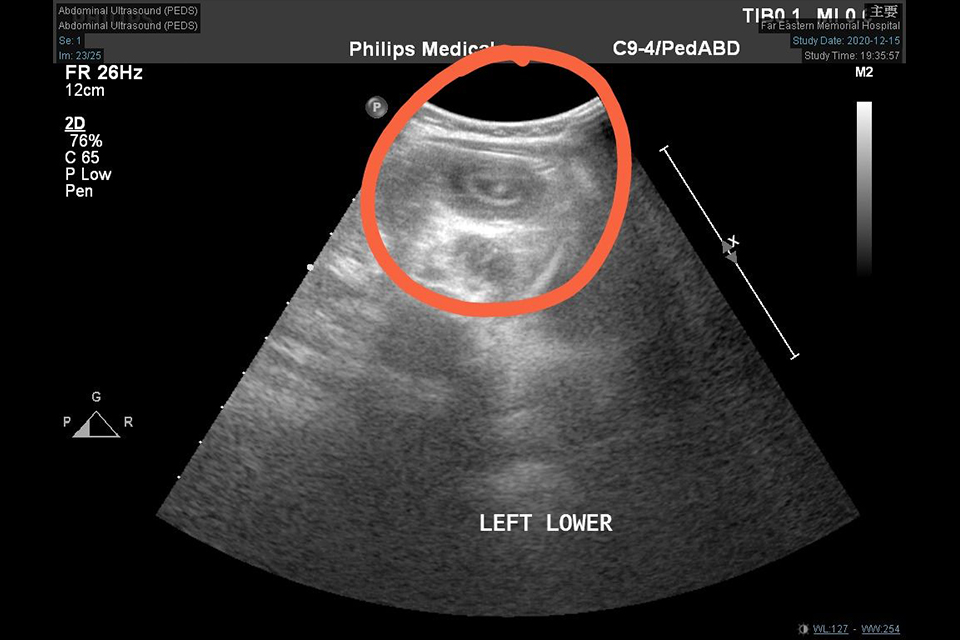

亞東醫院小兒科透過腹部超音波診斷腸套疊,檢查時會發現一段甜甜圈似的影像,由此確定診斷為腸套疊。在治療方面可以分為灌腸療法及外科療法。一般都先嚐試空氣或生理食鹽水灌腸,約70%至80%病例可以灌通,但有一些情形,並不適用灌腸方式,例如病人已有腹膜炎的症狀,或是發病時間太久且有明顯生理狀況不穩定的情形。